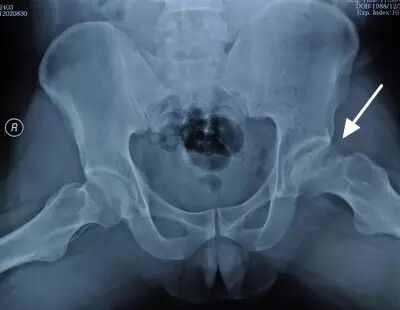

III期磁共振出现异常,X线片显示软骨下塌陷(新月征),股骨头内出现空洞,股骨头没有变扁

II期和III期的患者治疗方法相同,因为此时股骨头虽然还没有变形,暂时还不需要行人工关节置换术,但是股骨头已经出现空洞,随时股骨头就会塌陷变形,所以单纯的股骨头减压术是不能达到治疗效果的。这时就需要在股骨头减压的同时,植入一根支撑棒,顶住股骨头空洞区,防止股骨头在负重的情况下过早塌陷。其他治疗同之前相同,口服以上药物,定期复查,密切观察病情发展,尽量避免重体力劳动和爬山爬楼。

以上为股骨头坏死减压加支撑棒植入术示意图和术后X线片